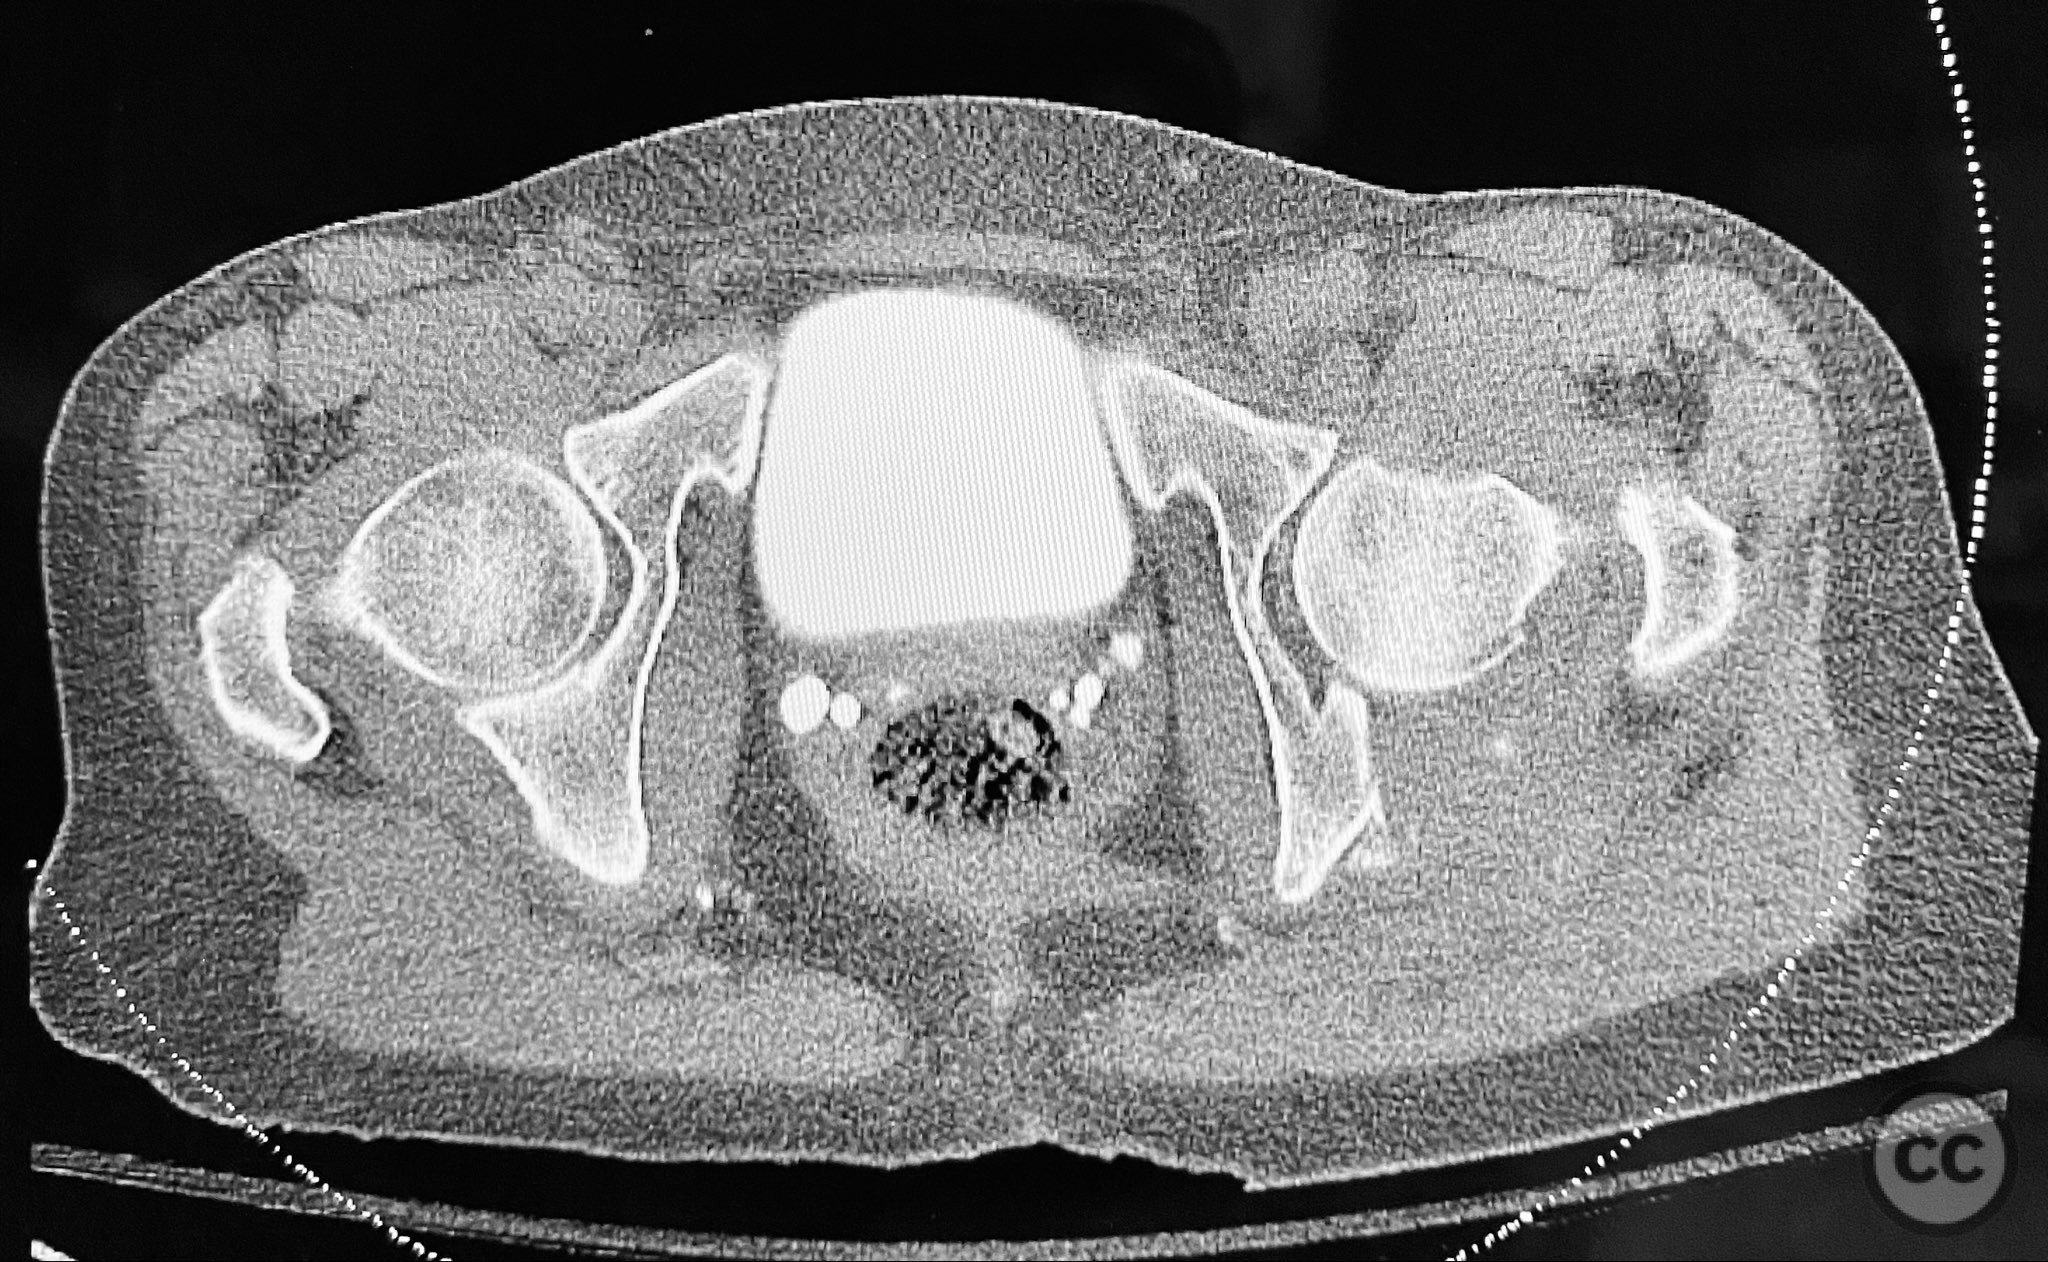

Clinical and radiological findings:  A patient sustained a posterior wall acetabular fracture-dislocation, characterized by comminution of the posterior wall, impaction of fragments into the posterior column region, and intra-articular loose fragments within the fossa acetabuli. Sagittal imaging demonstrated femoral head impalement on the intact wall, raising concern for potential irreducibility. Coronal and axial CT images revealed acetabular and femoral head impactions, peripheral wall comminution, incomplete fracture extension at the acetabular notch and quadrilateral surface, and an articular fragment within the joint. Surface renderings confirmed the extent of peripheral wall comminution and impaction. Despite these findings, a closed manipulative reduction was successfully achieved, resulting in a congruent reduction on post-reduction imaging.